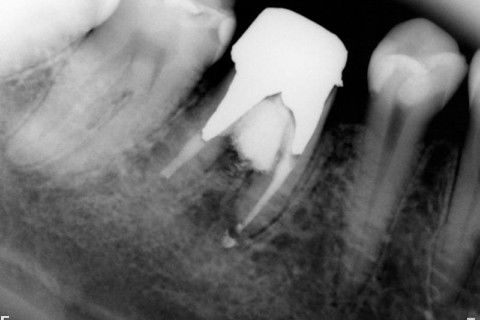

Retratamento de Canal, Tratamento de Perfuração, Restauração Provisória com Resina, Núcleo e Provisório.

RETRATAMENTO DE CANAL, TRATAMENTO DE PERFURAÇÃO, RESTAURAÇÃO PROVISÓRIA COM RESINA, NUCLEO E PROVISÓRIO.